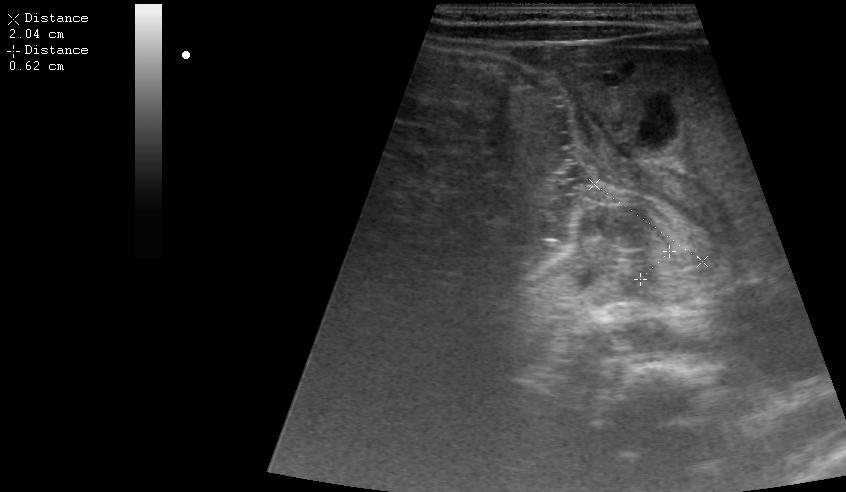

Ребёнок 1 месяц 10 дней от родy, с отсуствием прибавки в весе.

Hypertrophic pyloric stenosis.

Criteria:

1.Pyloric channel > 12 mm in length

2.Muscular layer thickness > 3-4 mm

3.Donuts sign at transverse scanning